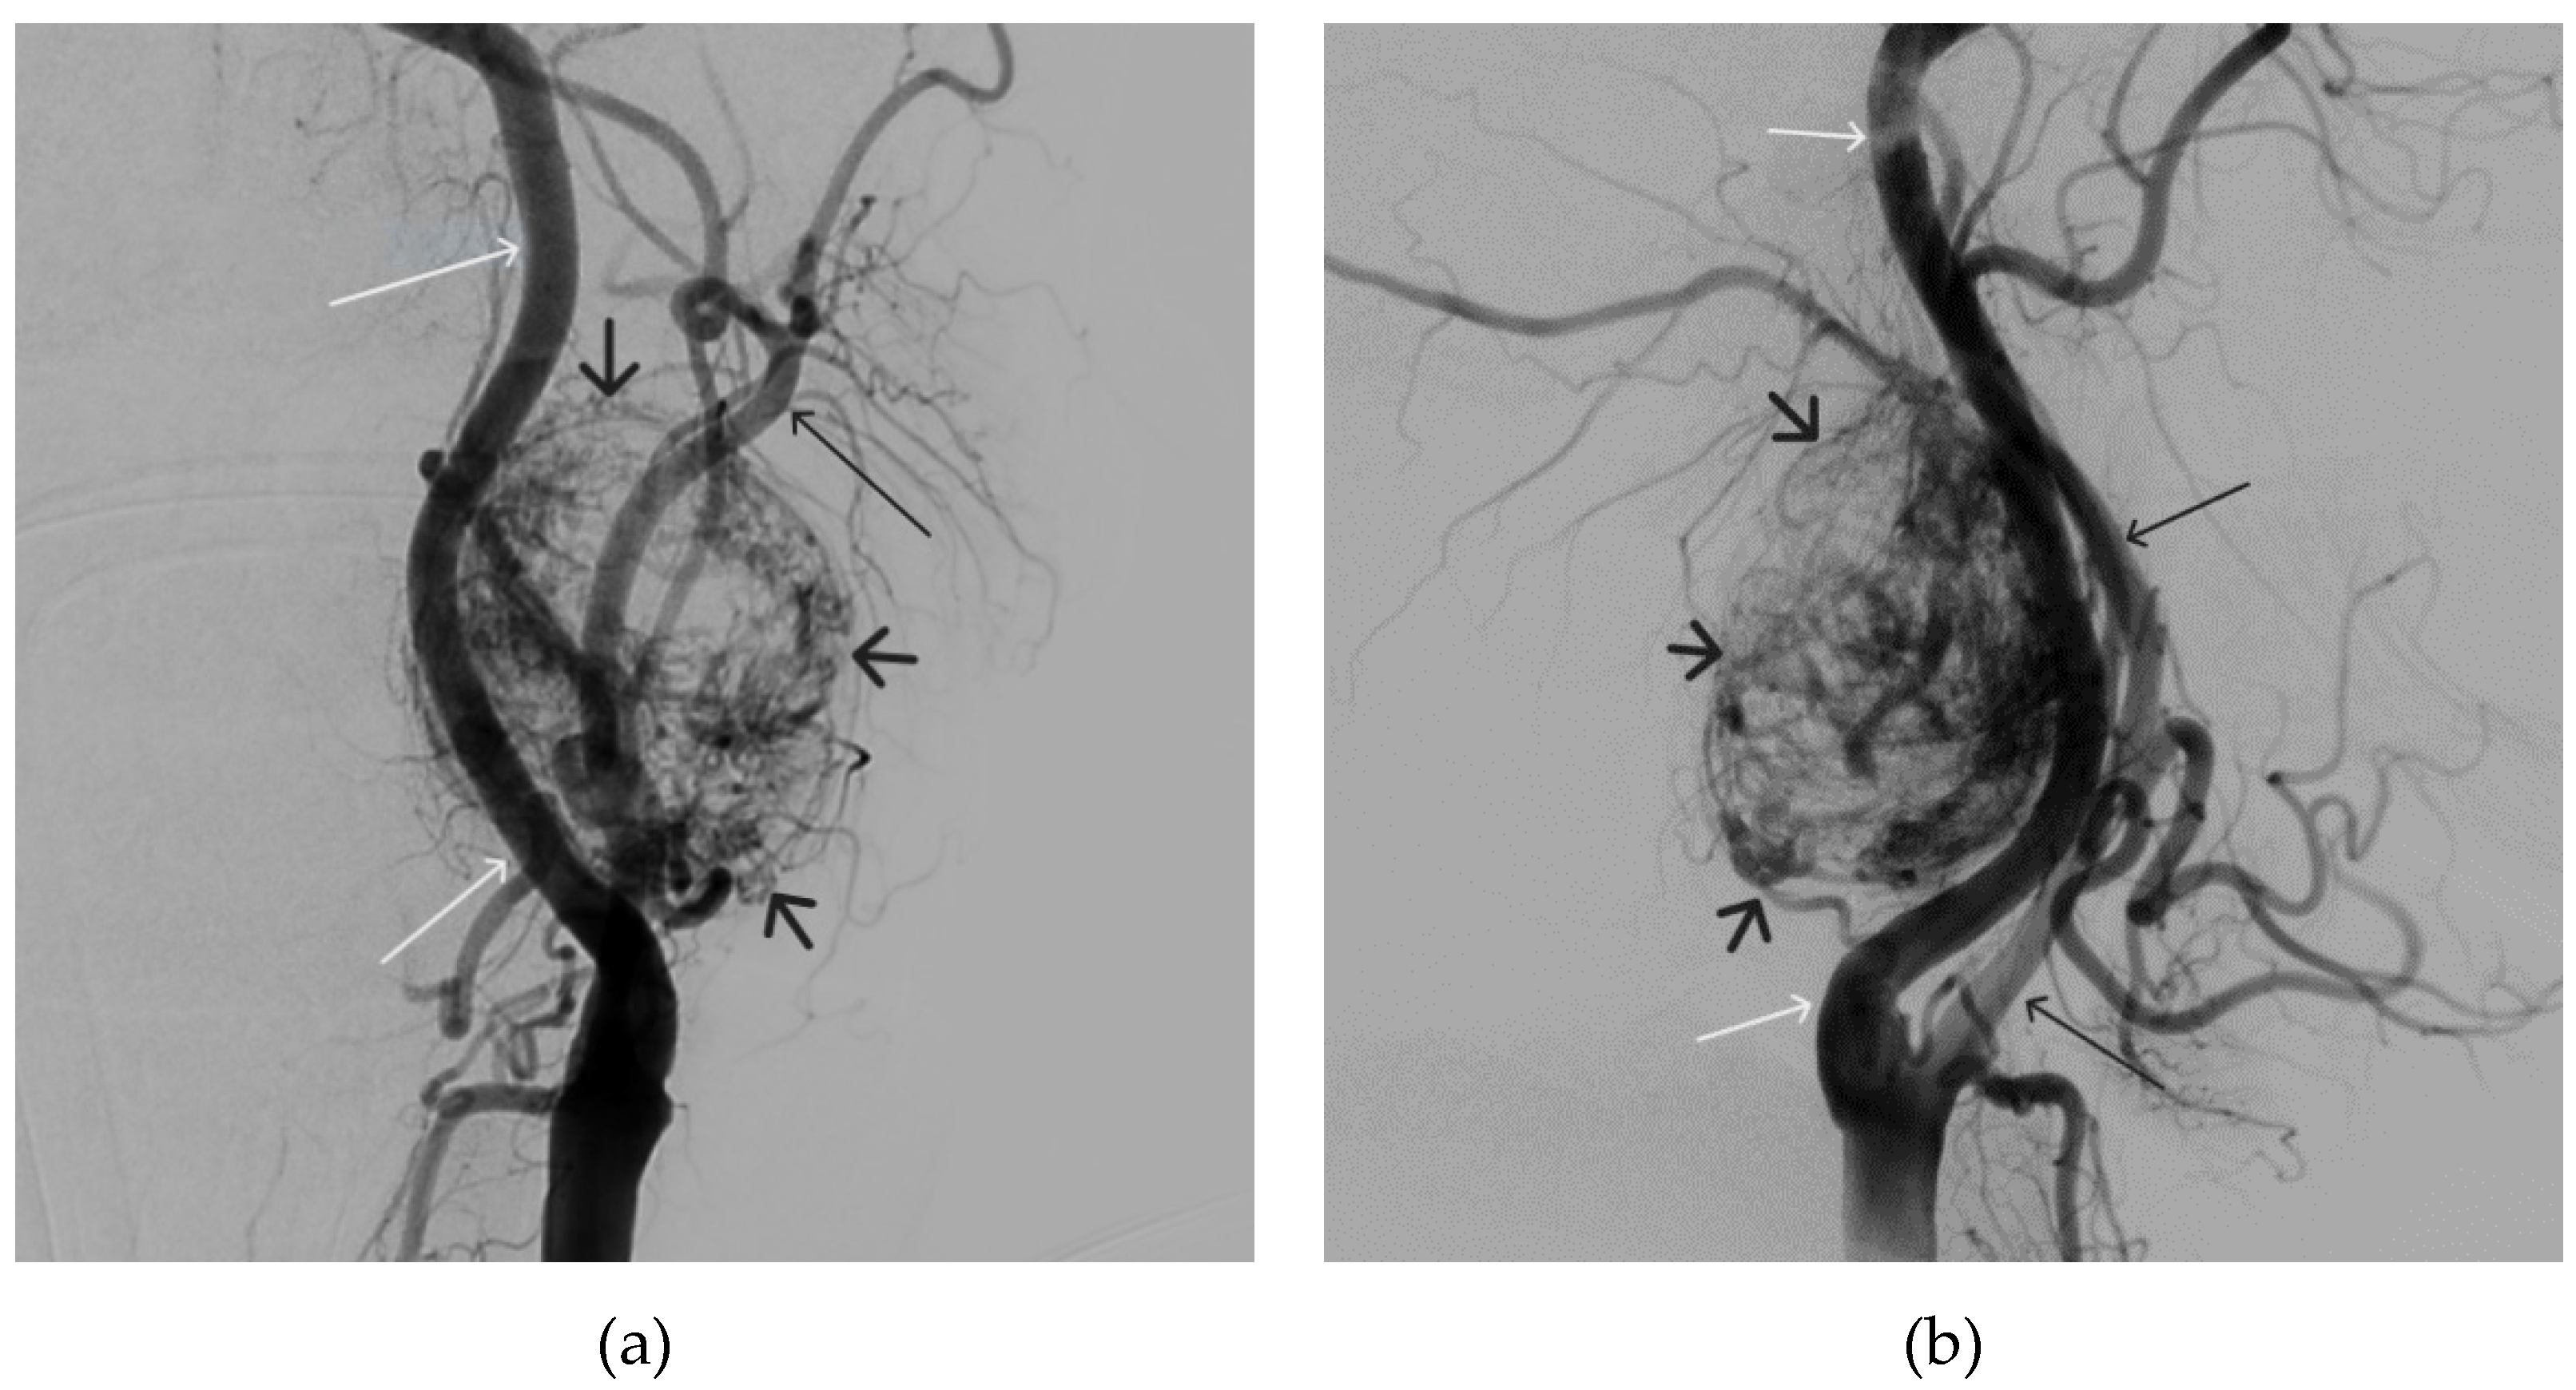

Figure 11. Digital subtraction angiography from the left common carotid artery: a – direct projection, b - lateral projection (white arrows indicate the left internal carotid artery, long black arrows indicate the external carotid artery, short black arrows indicate the boundaries of the paraganglioma).